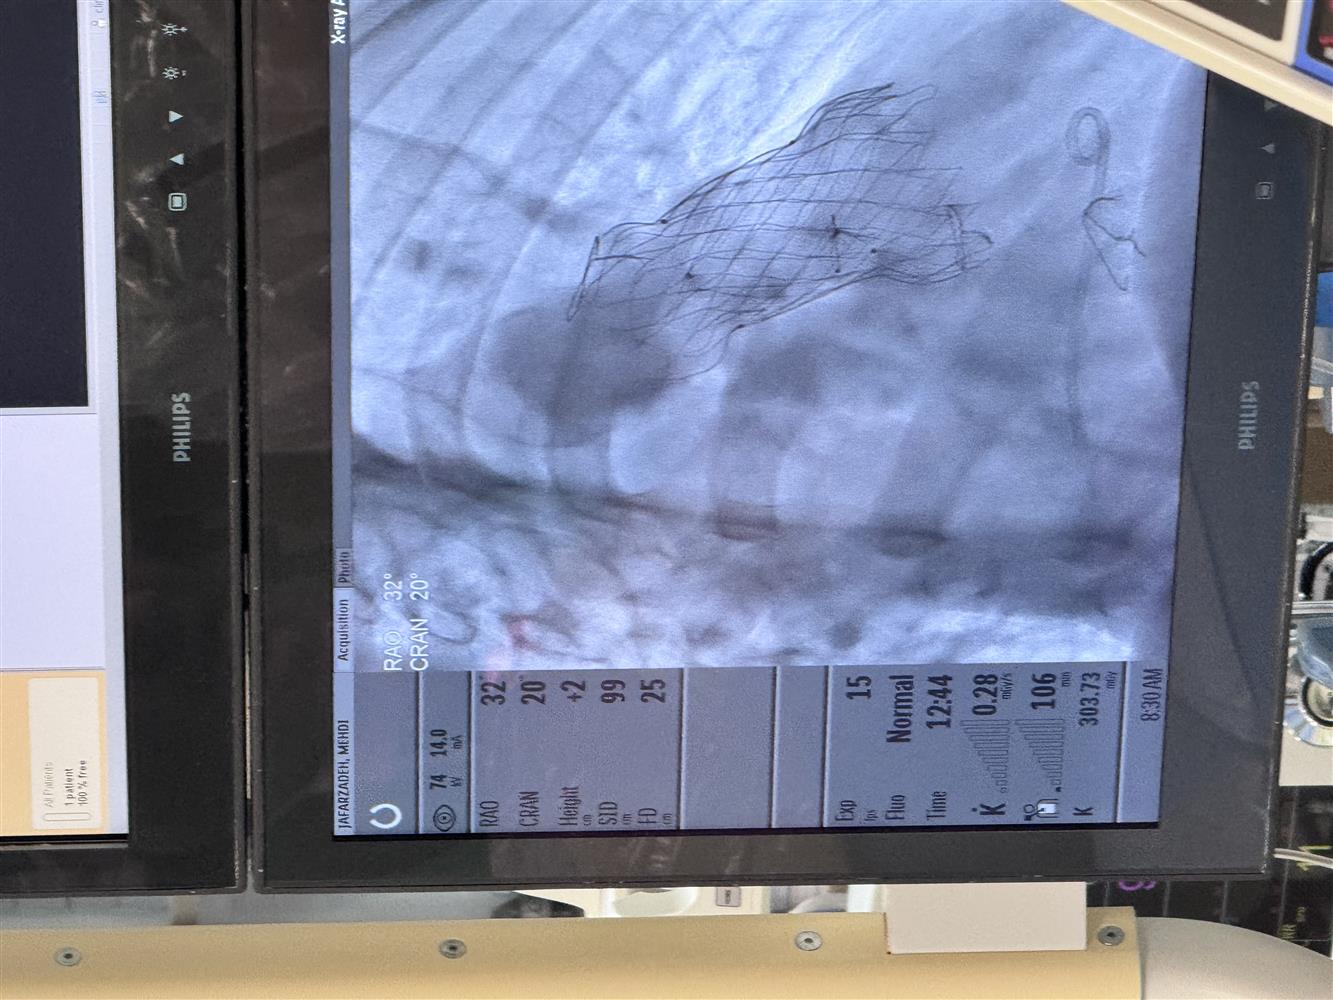

جراحی فوق پیشرفته پیوند دریچه مصنوعی قلب با موفقیت در بیمارستان فوق تخصصی مدائن انجام شد.

به گزارش روابط عمومی بیمارستان فوق تخصصی مدائن جراحی فوق پیشرفته پیوند دریچه مصنوعی قلب با موفقیت در  بیمارستان فوق تخصصی  مدائن انجام شد.

این پروسیجر پیشرفته در سرویس فوق تخصصی قلب و عروق بیمارستان فوق تخصصی مدائن زیر نظر مستقیم دکتر علی اکبر زینالو فوق تخصص قلب کودکان برای بیمار با سابقه مادرزادی تترالوژی فالوت قلب جهت جاگذاری دریچه مصنوعی فلزی از طریق اینترونشن با نتیجه بسیار خوب انجام شد.

این اقدام که در سطح کشور بسیار کم انجام میشود گامی مهم در ارتقاء خدمات درمانی بیماران قلب و عروق به شمار می رود.